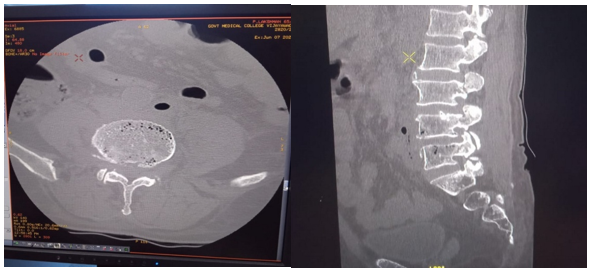

He got a plain radiograph of the thoracolumbar spine and was within normal limit. On CT scan (Figure 1), multiple air pockets were noted in L4 & L5 vertebrae.

Figure 1 CT scan of lumbar vertebrae.